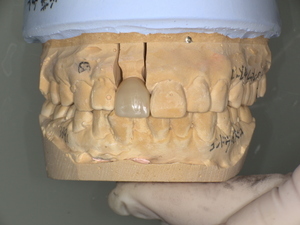

①支台築造(歯の土台作り)

歯の欠損が大きかったため、まず歯の土台を作りました。

②歯の形成

被せ物を装着するため歯の形を整えます。

③精密な型取り

シリコーン印象材を使用して精密な型取りを行いました。